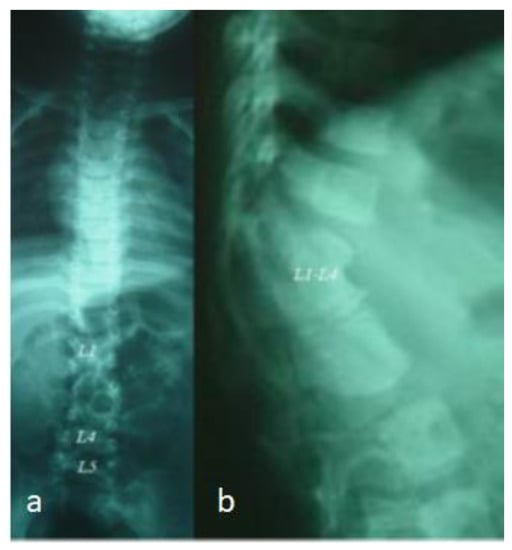

3.4. Parry–Romberg Disease (Birth Defects Possibly in Correlation with Pre-Gestational Diabetes)

A 4-year-old girl presented with progressive unilateral left sided facial atrophy (fronto-maxillary defects), which was falsely diagnosed as facial diplegia. She was born full term as a product of a fluctuating non-controllable maternal diabetes. Her subsequent course of development was with normal parameters. After the age of three and a half years, her parents observed a progressive symmetry of the face. The mother said that her daughter had an unusual rise in temperature for one week, followed by a gradual and slowly progressive loss of subcutaneous fat and muscle of the right side of the face, and she started to complain of cluster headaches (Figure 9a). There was no history of convulsions or any neurological deficits. The family history showed migraine as a uniform complaint in her mother and all aunts and uncles, and a ruptured cerebral aneurysm was the reason for the death of a young cousin. Interestingly, uncontrolled fluctuating pregestational diabetes mellitus was identified. A clinical examination showed a growth deficiency and unilateral facial atrophy of the right side of the face (progressive weakness and atrophy of the masticatory muscles, associated with a noticeable retardation of ipsilateral tooth eruption). An examination of the buccal cavity revealed right sided tongue atrophy. Palpation of the jaw showed apparent hypoplasia. A musculo-skeletal examination showed moderate ligamentous hyperlaxity and small hands and feet. Interestingly, lumbar kyphosis was evident. Skeletal survey: the AP skull radiograph showed apparent atrophy of the right side of the mandible, giving rise to micrognathia (right sided atrophy of the maxilla, and the alveolar process of the maxilla) (Figure 9b). An AP spine radiograph showed diffuse malsegmentation of L1–4 and spina bifida occulta of L5 (Figure 10a). A lateral spine radiograph showed progressive lumbar kyphosis (Figure 10b). Whole exome sequencing and the FISH test did not reveal positive results.

Figure 10. AP spine radiograph showed diffuse malsegmentation of L1–4 and spina bifida occulta of L5 (a); Lateral spine radiograph showed progressive lumbar kyphosis (b).